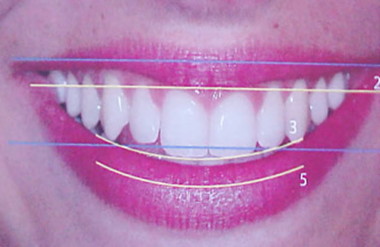

Este é o sorriso que todas pessoas buscam. Perde-lo por negligência ou mau hábitos e muito fácil, recupera-lo é uma arte. Envolve numerosos procedimentos e muitas vezes com um alto custo. Prevenir e manter os dentes, portanto, é fundamental para auto-estima e principalmente para saúde e qualidade de vida.

Independete dos métodos usados durante as reabilitações, as linhas do sorriso têm que ser respeitadas. O sorriso em qualquer profissão é sempre nosso principal cartão de visitas.

As linhas que compõem um sorriso normal são estudadas cientificamente pelos profissionais da Odontologia. Todos aspectos relativos à sua recuperação são determinados pelos profissionais, e os tratamentos para sua execução são multidisciplinares, exigindo uma equipe odontológica competente e dedicada.